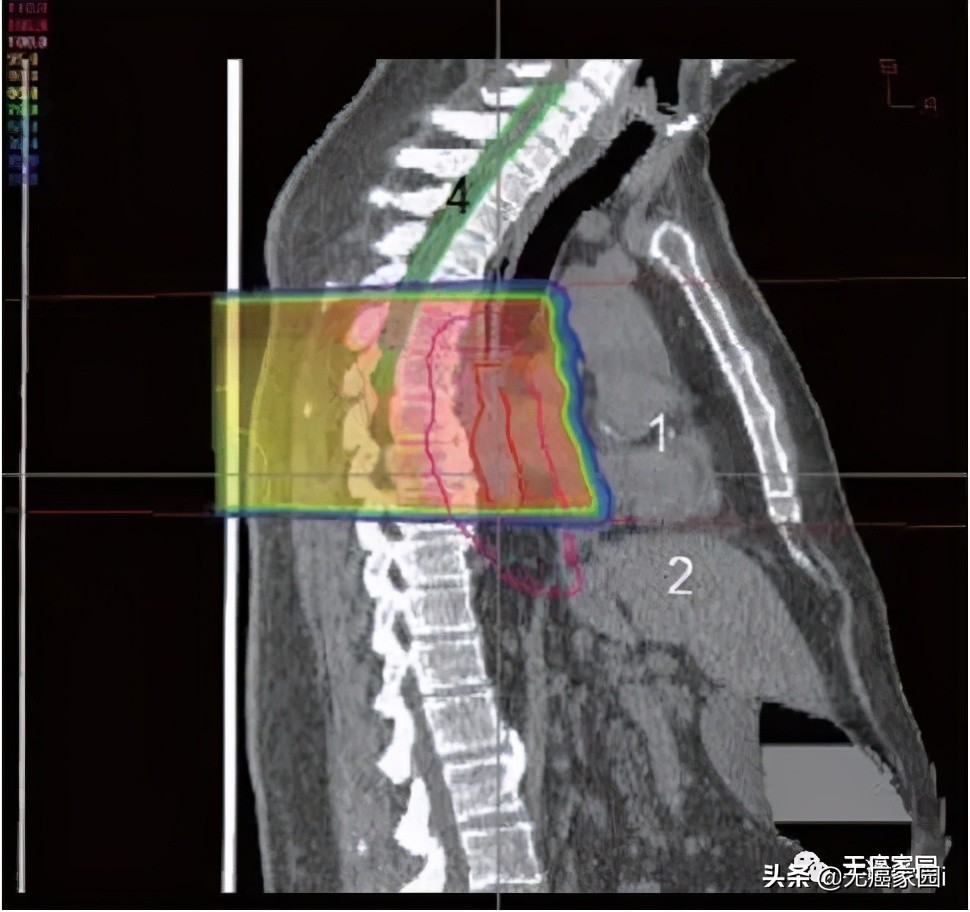

食道位于后纵隔内,靠近几个关键结构,即肺、脊髓和心脏。最大限度地减少对这些关键结构的毒性降低了患者的整体治疗发病率和死亡率。然而,必须在放射野中考虑足够大的边缘以覆盖肿瘤区域和受累淋巴结,这使周围器官面临更大的风险。肺剂量是食管癌放射期间毒性的主要危险因素。为了将脊髓剂量保持在容许范围内,通常需要使用多个倾斜角度的光束(图1~3)。这就导致肺部接收到大量辐射剂量,从而产生放射性肺炎和术后肺部并发症。

图2:后质子束进入人体并到达食道后停止的矢状图;1. 心;2. 肝脏;4; 脊髓